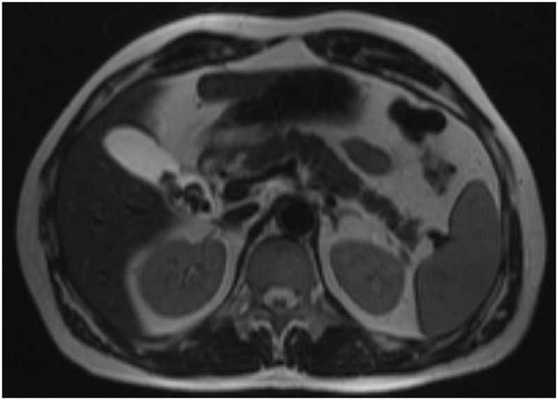

![МРТ брюшной полости]()

МРТ брюшной полости. На МР-томограмме в корональной плоскости отмечаются МР-признаки метастатического поражения брюшины в виде неправильно округлой формы узловых патологических образований (серый МР-сигнал на представленном изображении).